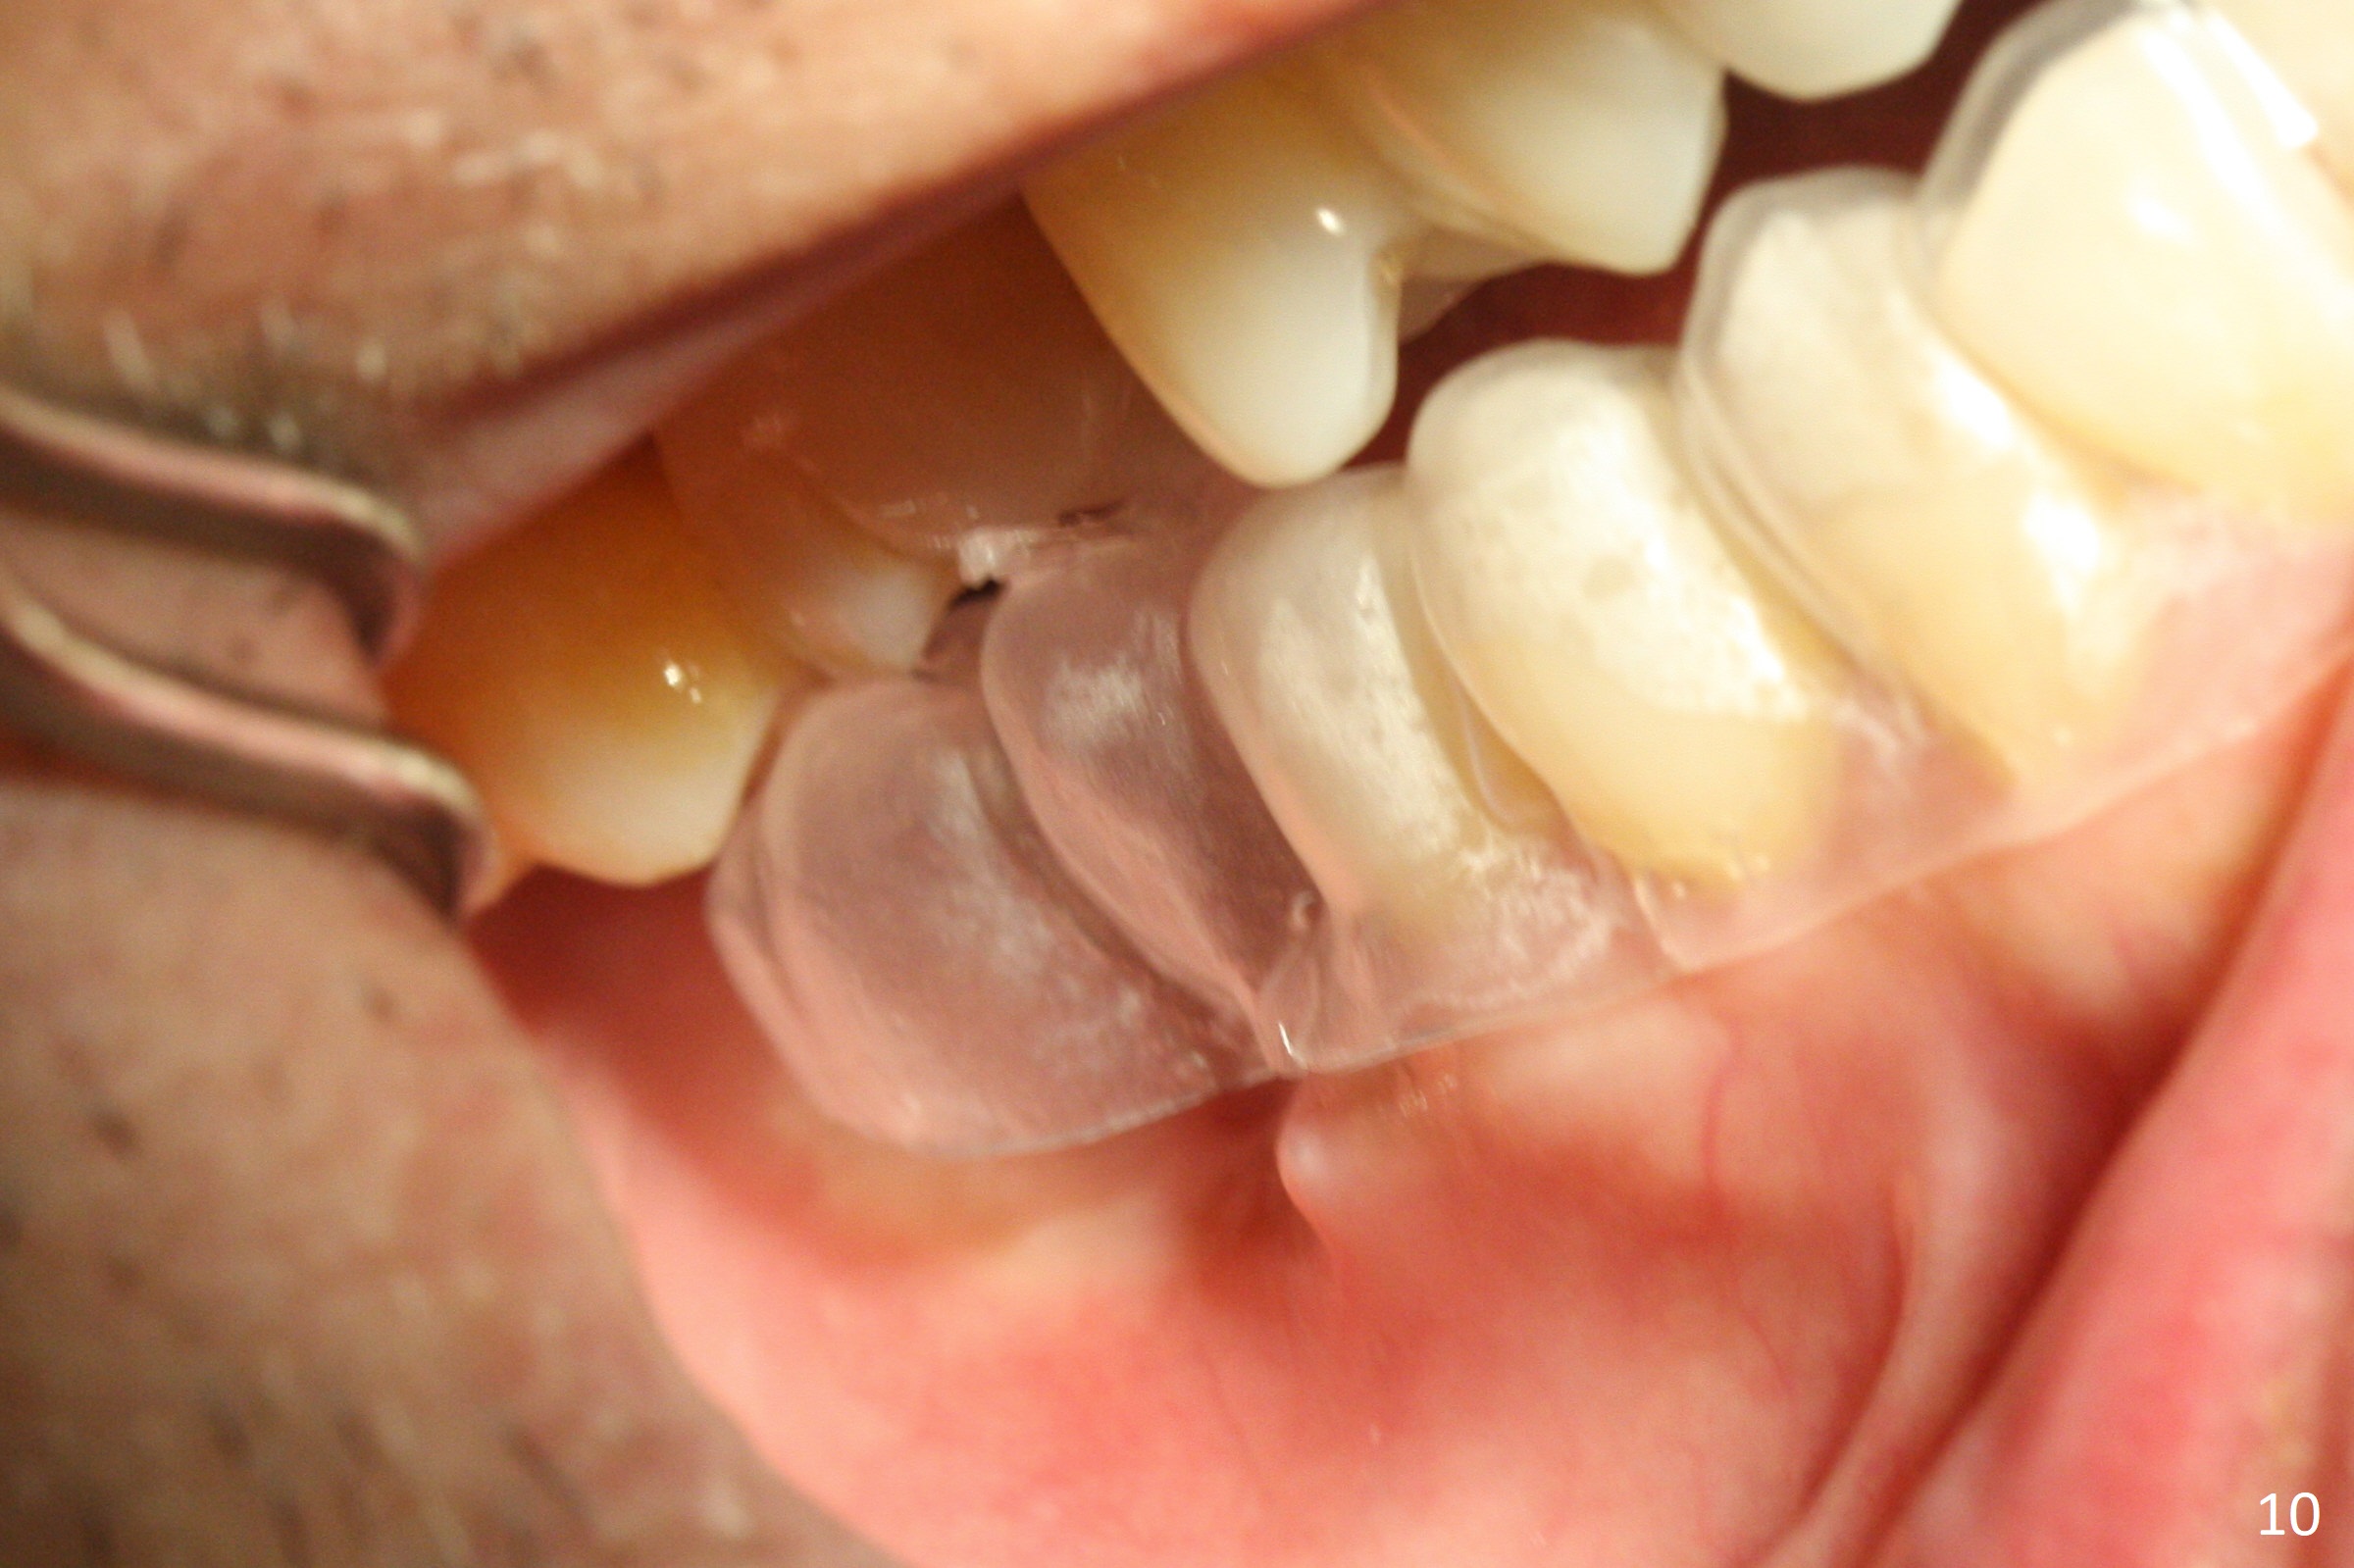

Extraction of the mobile tooth #31 (Fig.1) and debridement of the large socket are not difficult. But making osteotomy buccally does not seem to be easy. It will be difficult to restore. Instead, socket preservation is accomplished by filling the socket with approximately 1.5 cc of Mineralized Cortical/Cancellous allograft until the crest (Fig.2,5). The socket opening is closed by insertion of 4 pieces of PRF membranes (Fig.3) and 4-0 Chromic gut sutures (Fig.4). In the end of surgery, it appears that osteotomy in the center of the socket could be a better approach. Postop re-analysis of CT (Fig.6) and PA (Fig.7) shows that there is 3.9 mm of the native bone to support a 5.5x10 mm implant. Sinus Lift Master Kit should be used with 2 mm initial drill and 2.8 and 3.6 mm round drills with 4 mm stopper.

The socket heals 3 months postop (Fig.8,11). There is vertical loss of the ridge at #31 (Fig.9,10). The implant placed at #31 will be shorter than that at #30 (Fig.12). The patient will return for implant placement 4 months postop.